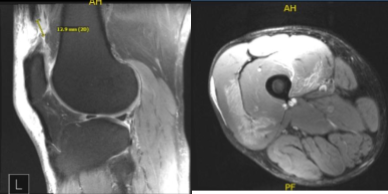

Xray and MRI results were presented and shown and no significant degenerative changes in the Xray. Meanwhile, MRI showed significant result of full-thickness rupture of the distal quadriceps tendon occurring 1.8 cm proximal to the patellar insertion site and resulting in a tear gap measuring up to 1.5 cm. There is accompanying patella Baja and soft tissue edema tracking into the vastus musculature and small to moderate-sized joint effusion.

MRI-3T Right Knee Non-contrast